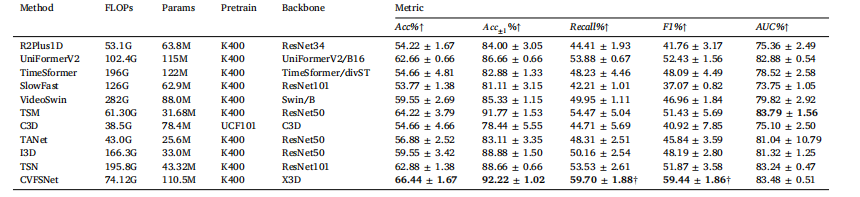

Table 4Quantitative comparison of the scoring performance of different methods on AmTICIS. † indicates significancy (𝜌 < 0.05). Best results are indicated in bold.

表4:在自动改良脑梗死溶栓分级评分(AmTICIS)数据集上,不同方法的评分性能的定量比较。†表示具有显著性((\rho < 0.05))。最优结果以粗体显示。